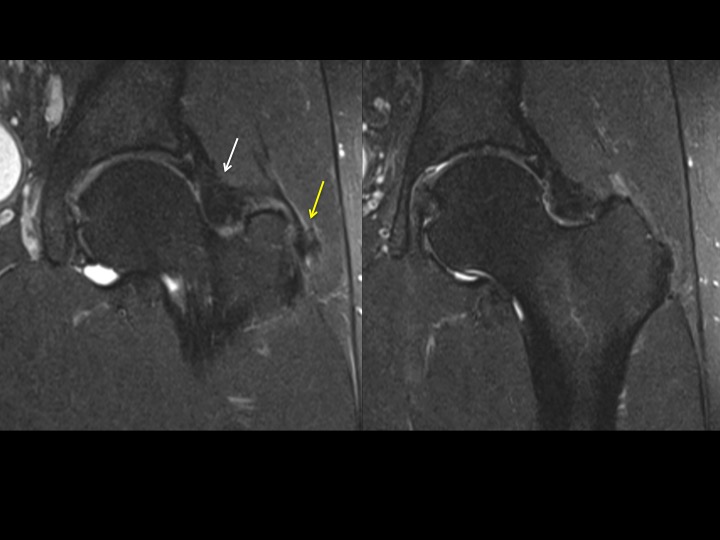

42M chronic pain with reported work injury 17 months ago

There is marked dark signal capsular thickening anteriorly and superiorly (white arrows). The reference, based on arthrography, refers to much thinner capsular measurements, and does not specify where measurements are made (these are mid superior and anterior). Is this chronic adhesive capsulitis? There is also insertional G Minimus tendinosis (yellow arrows) and degenerative tearing of the anterior labrum. The patient specified that pain is worst posteriorly. Last image from a different patient today with comparatively normal appearing capsule. Reference article.